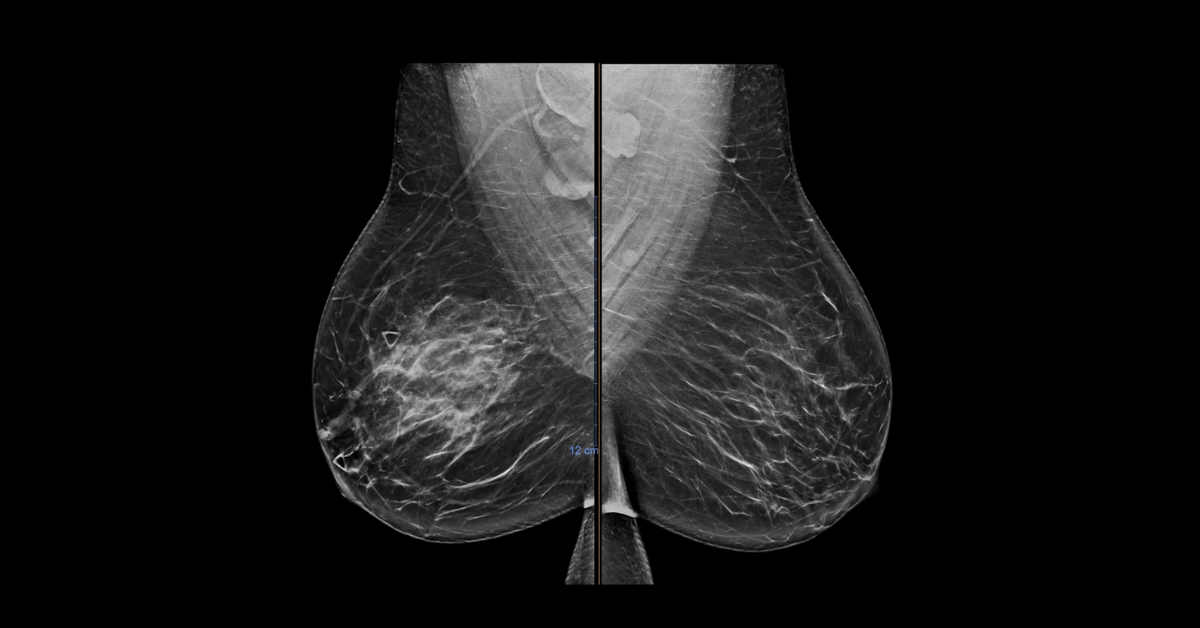

In this CME course we will review five pediatric breast cases presented by order of ascending age. These cases are either uncommon or common but uncommonly imaged and therefore unfamiliar to many radiologists.

1. Recognize and diagnose neonatal breast enlargement

2. Understand the ultrasound appearance of normal breast development through Tanner stages

3. Review the appropriate workup of a palpable abnormality in a female patient less than 30 years of age